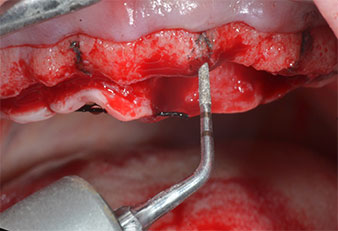

A flame-shaped, diamond-coated piezoelectric instrument (Piezomed I1) was used to mark the implant positions and to perform pilot preparation (Fig. 3). Care was taken to use an up and down movement, with reduced power, full irrigation and low pressure (below 300 g). Next a pilot instrument (Piezomed I2A/I2P) was applied for the initial 2 mm diameter enlargement of the implant sites (Fig. 4), followed by a 3 mm insert (Fig. 5).

Ultrasonic marker instrument Piezomed

Fig. 3: Preparation with the ultrasonic marker instrument Piezomed I1 is performed in an up and down movement, parallel to the long axis of the working part.

Piezomed I2A/I2P instruments

Fig. 4: The next step is pilot enlargement with the Piezomed I2A/I2P instruments, which are applied in a rotary horizontal movement.